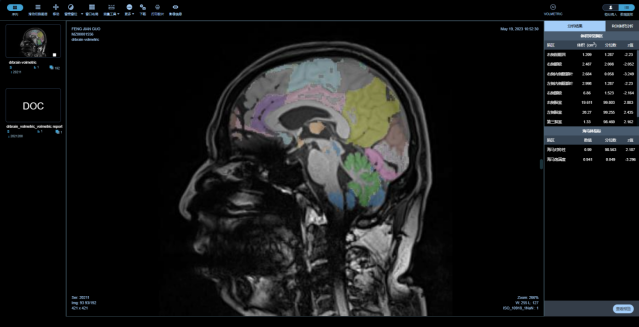

中樞神經(jīng)系統(tǒng)核磁影像AI診斷分析平臺

是專注在中樞神經(jīng)系統(tǒng)疾病的人工智能診斷分析平臺,基于醫(yī)未自行搭建的全年齡段中國人群全腦結(jié)構(gòu)影像數(shù)據(jù)庫,結(jié)合前沿的大數(shù)據(jù)分析和人工智能等核心技術(shù),快速、精準(zhǔn)評估全腦結(jié)構(gòu)變化、腦白質(zhì)病變、微出血灶及腦血流量等,以量化、直觀的結(jié)果,輔助臨床做出超早期的精準(zhǔn)診斷及疾病進(jìn)展預(yù)測。

最全面的分區(qū)

最全面的腦結(jié)構(gòu)分區(qū),快速獲取全腦100個精細(xì)腦區(qū)共165項指標(biāo),精度達(dá)到毫米級